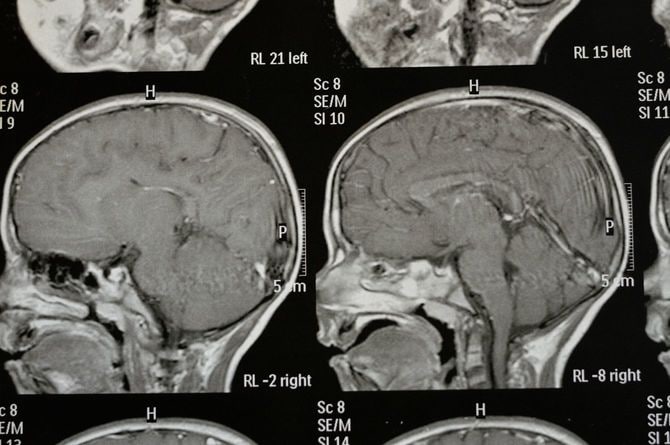

シャント手術を受けた母親だったが、記憶力などはやや回復したものの、「年齢相応よりも物忘れがある」と評価され、「軽度認知症」と診断。